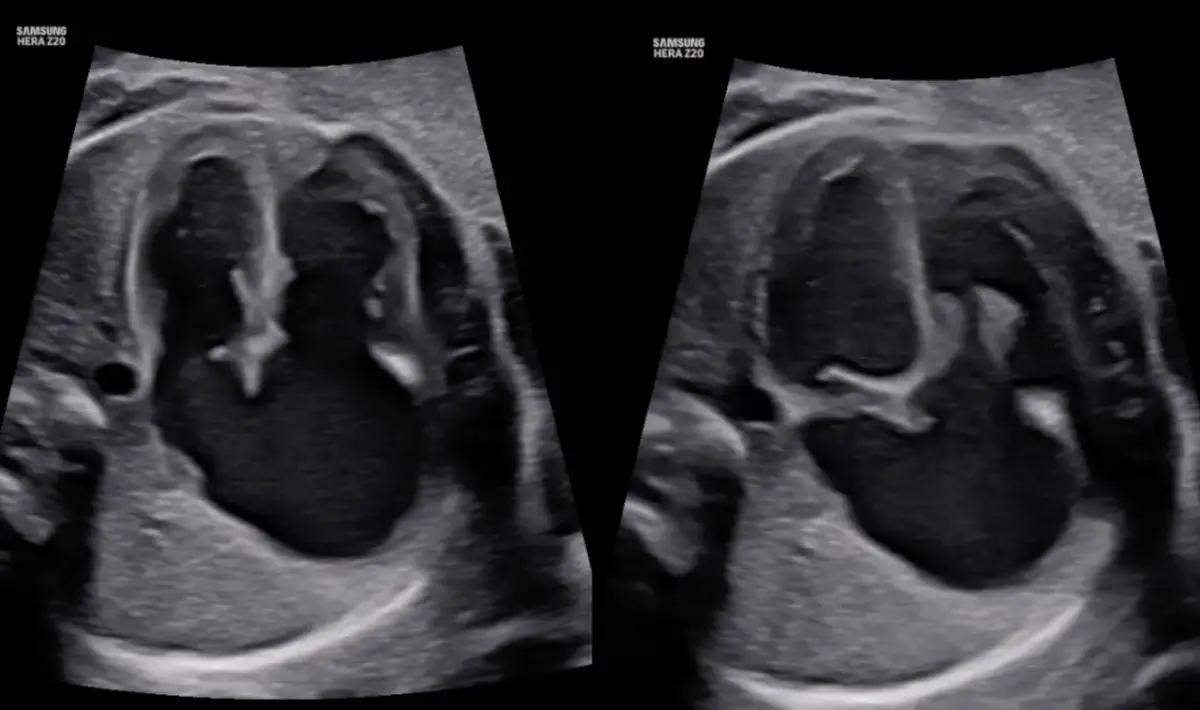

Oczywiście, zawsze rozważane są bezpieczniejsze alternatywy dla badania RTG w ciąży, takie jak na przykład USG płuc. Jednakże, w wielu schorzeniach klatki piersiowej, RTG pozostaje złotym standardem diagnostycznym, którego nie zawsze da się zastąpić. Ultrasonografia płuc, choć bezpromienna, ma ograniczenia w ocenie pewnych struktur i patologii, dlatego decyzja o wyborze metody zawsze należy do lekarza, który kieruje się dobrem pacjentki i dziecka.